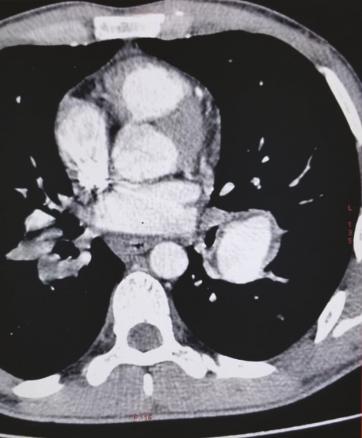

Cet homme de 21 ans consultait pour des hémoptysies. Il avait comme antécédent une aphtose bipolaire. L’électrocardiogramme était en rythme sinusal et l’échocardiographie (fig. 1 ) montrait un énorme thrombus du ventricule droit et de la veine cave inférieure. Sur l’angiotomodensitométrie thoracique (fig. 2 ), on notait de multiples anévrismes des artères pulmonaires. Le diagnostic de maladie de Behçet était retenu devant la thrombose intracardiaque, l’antécédent d’aphtose bipolaire, une uvéite antérieure et le test de sensibilité cutanée. Le patient était mis sous corticothérapie, colchicine et anticoagulation avec une bonne évolution clinique et la persistance du thrombus cardiaque. Le malade était adressé pour une thrombectomie chirurgicale.